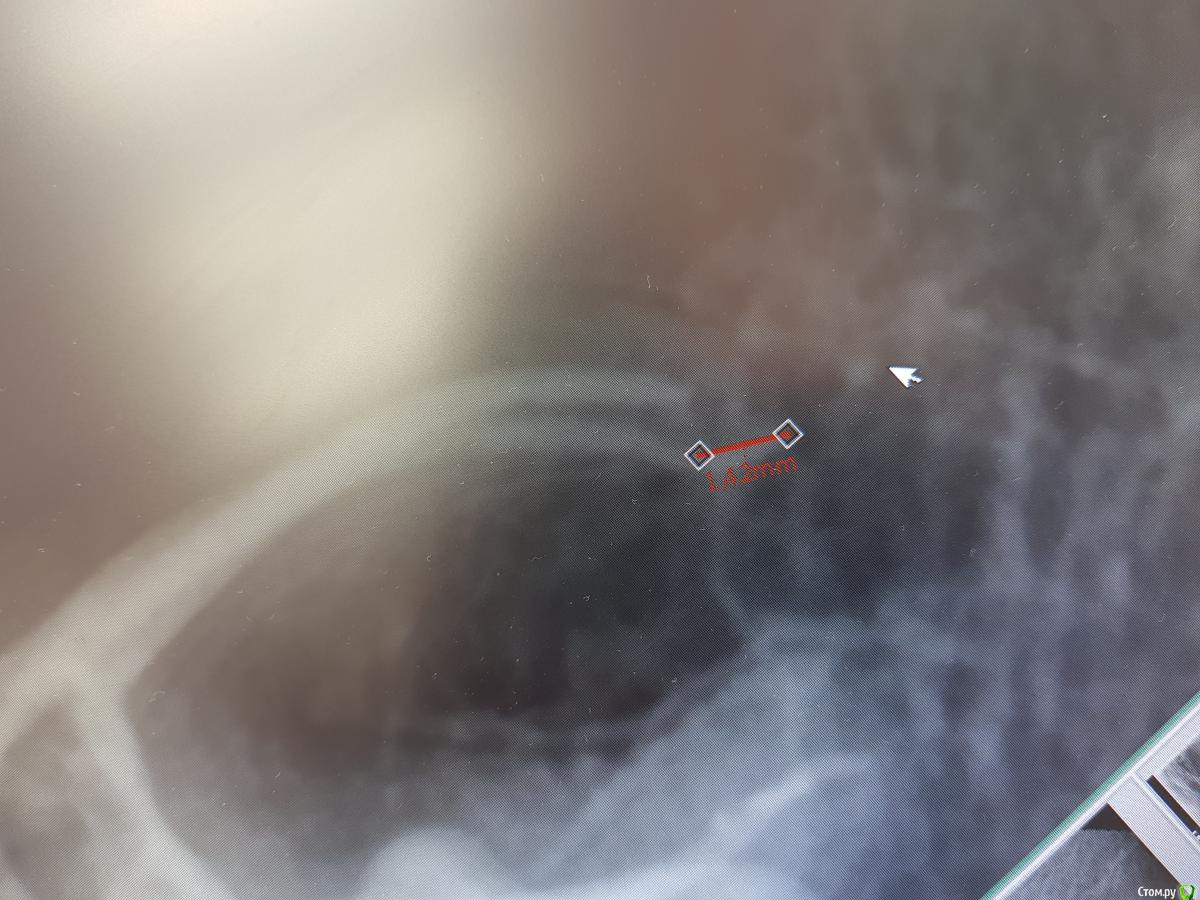

Zemtsov.alexander Опубликовано 28 августа, 2019 Поделиться Опубликовано 28 августа, 2019 Всем доброго времени суток, лечил 46 зуб по поводу пульпита, при вертикальной пломбировки вывел в медально-язычном канале гуттаперчу за верхушку, ваши прогнозы, какой ваш опыт в таких ситуациях? Пациент был неделю спустя, первые 2 дня зуб реагировал при накусывании, сейчас боль почти сошла на нет. Ссылка на комментарий

Zemtsov.alexander Опубликовано 23 октября, 2019 Автор Поделиться Опубликовано 23 октября, 2019 Спустя два месяца пациент пришёл на осмотр, есть лёгкая реакция на перкуссию. Судя по снимку есть воспаление на 45 зубе, но реагирует именно 46 Ссылка на комментарий

Zemtsov.alexander Опубликовано 23 октября, 2019 Автор Поделиться Опубликовано 23 октября, 2019 Вот панорамный снимок Ссылка на комментарий